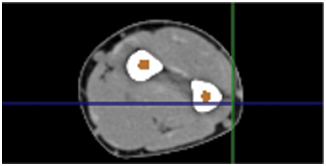

Currently the ability to understand the mechanical behavior of the various components of the human body is in a process of continuous improvement. This is why a methodology for establishing the steps of the biomodeling of cortical and trabecular tissues from tomography to the construction of a solid for analysis with the finite element method and the interpretation of the results obtained to understand the behavior of each bone tissue separately.1 The construction of a bone model begins from filling areas in tomography using the Scan IP® program (Figure 1) which can recognize DICOM formats to generate a point cloud which will be transformed into an STL format (Figure 2) to be recognized by the Power Shape computational system® and thus begin to build a shell for export in ANSYS® and perform the corresponding numerical analyses.2